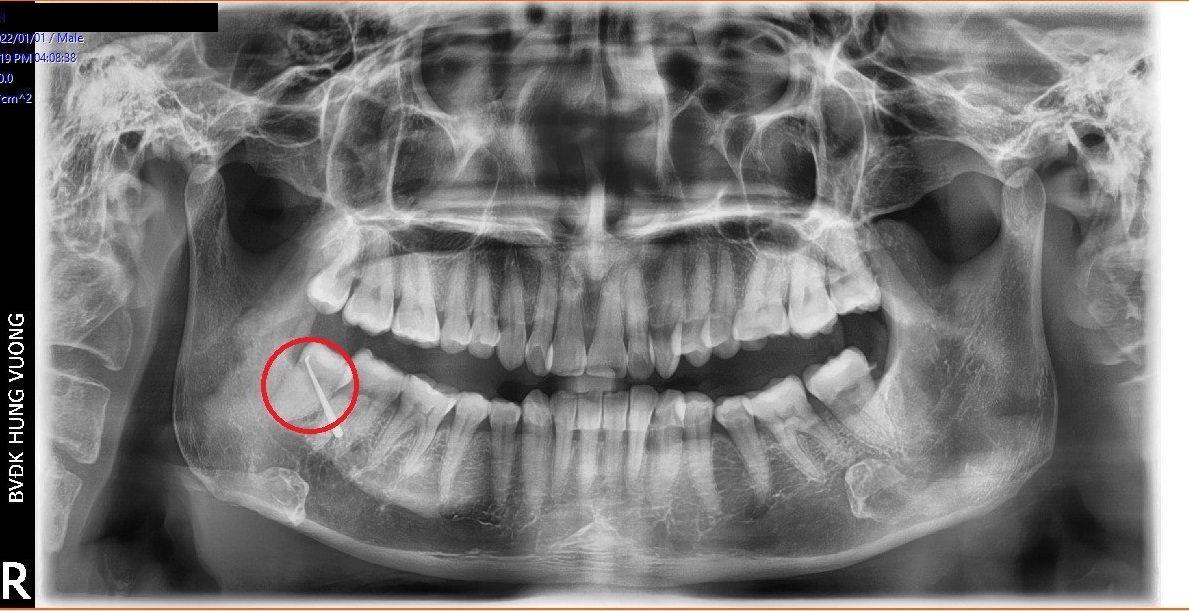

Đến Bệnh viện đa khoa Hùng Vương (Phú Thọ) thăm khám, bệnh nhân được chỉ định nhập viện điều trị ngay với chẩn đoán: Áp xe vùng má phải do răng số 48 mọc lệch.